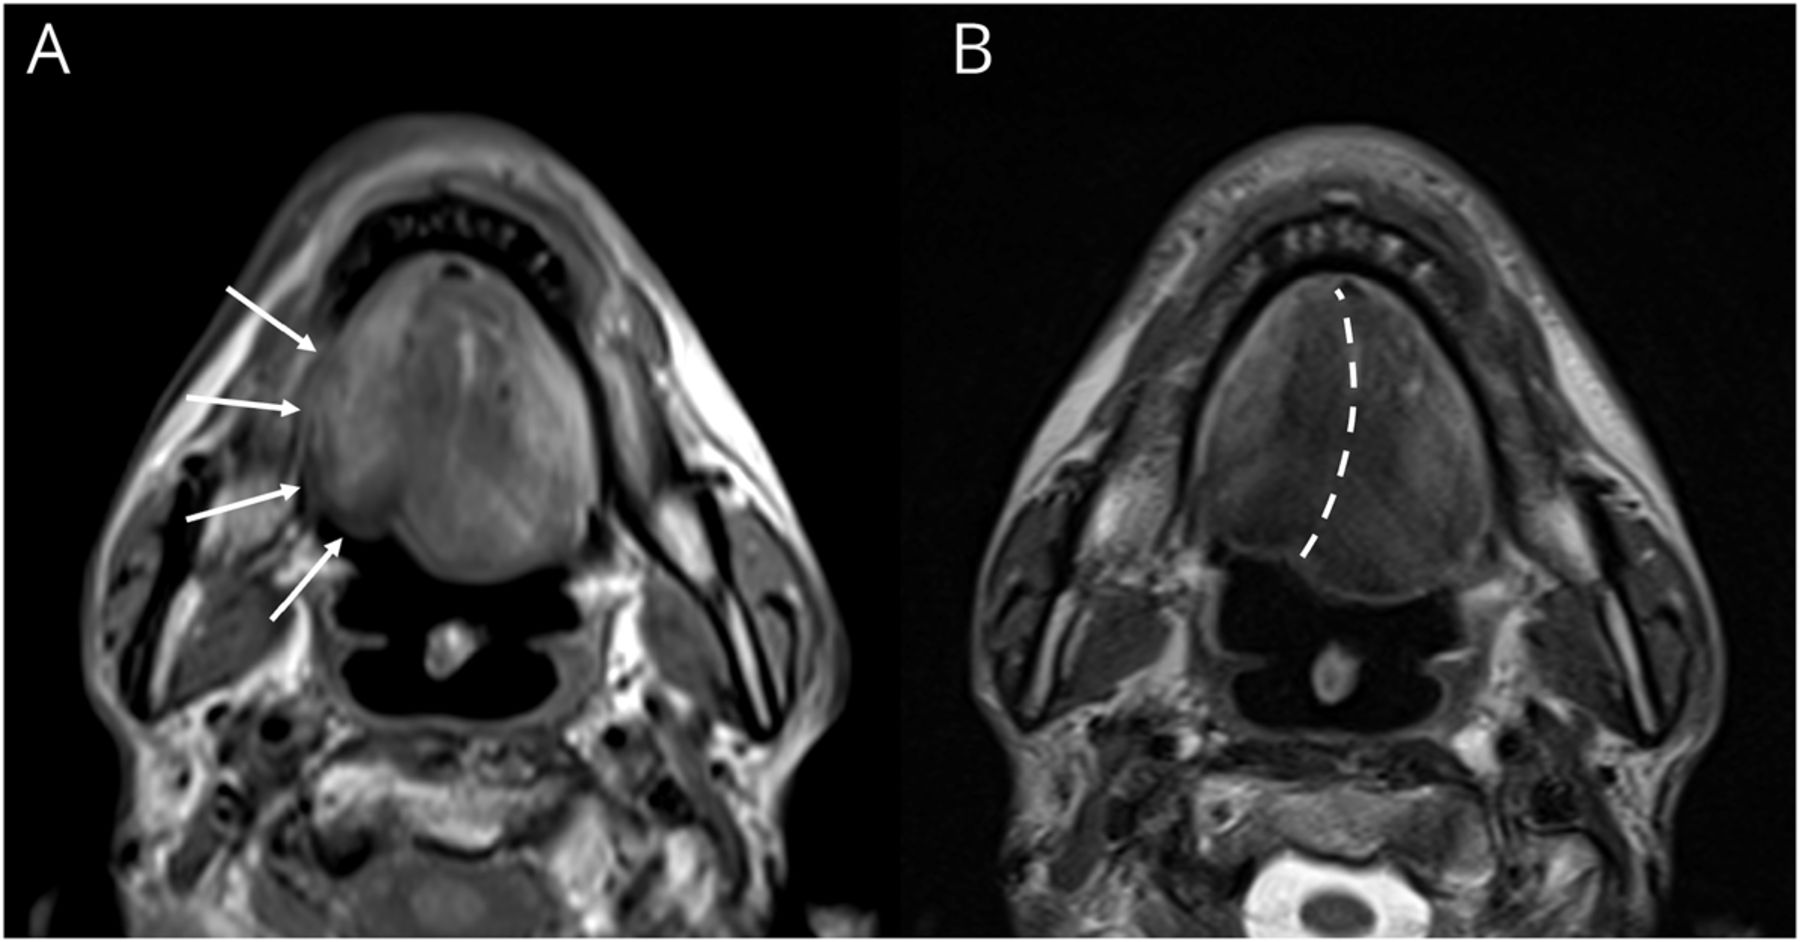

一位49岁的未分化鼻咽癌患者接受了2个周期的化疗,随后进行了右侧头颈部放射治疗。13年后,他出现了进行性吞咽困难和构音障碍。神经学检查显示萎缩伴波状运动及右侧舌部明显波纹;针刺肌电图显示右侧颏舌肌(视频1)。头颈部MRI证实孤立单侧舌萎缩(数字),而喉镜检查显示吞咽开始延迟和喉抬高降低。

右侧舌萎缩和肌萎缩(第1部分)。右侧颏舌肌的针刺肌电图显示,肌萎缩性放电由单个运动单位电位的重复爆发组成,以规律的间隔(每秒3次)发生,内爆发频率约为50 Hz(第2部分)。下载补充短片1通过http://dx.doi.org/10.1212/201607_Video_1